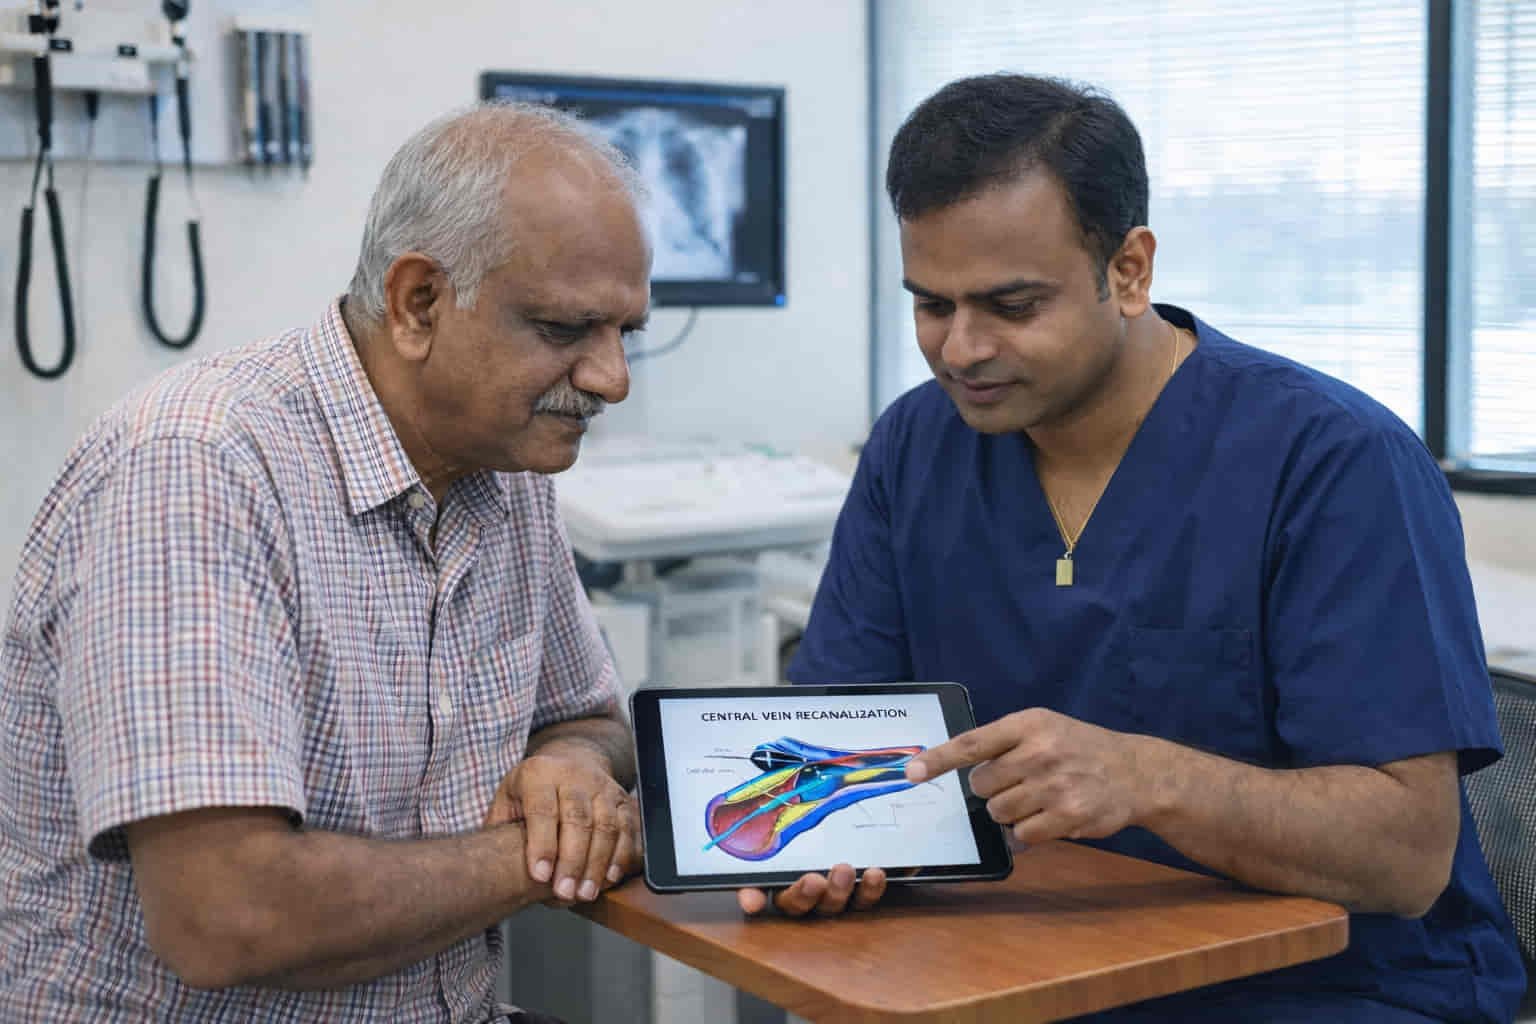

Globally recognized innovator, Dr. Ram K Gurajala MD, leads the frontier with patented technologies, 40+ pioneering publications, and breakthroughs that redefine vascular care for patients in Hyderabad, Chennai, and across India.

A Translumbar Venous Catheter provides a critical solution when traditional access points are exhausted. Instead of the neck or chest, a specialized catheter is placed directly into the Inferior Vena Cava (IVC) through the lower back, giving immediate, high-flow access for dialysis or essential infusions.

The procedure is performed under precision guidance in our advanced suites in Hyderabad and Chennai:

Facing blocked veins and limited options in Hyderabad or Chennai? There is a way forward. Consult Dr. Ram Kishore Gurajala at ir4ubyram to see if a Translumbar Venous Catheter—a specialized ‘back-entry’ lifeline—is the stable, long-term solution you’ve been searching for.